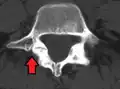

Anterolisthesis L5/S1

Anterolisthesis L5/S1. Blue arrow normal pars interarticularis. Red arrow is a break in pars interarticularis.